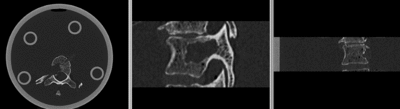

original unregistered unregistered

registered (after flipping axis and cropping volume) registered